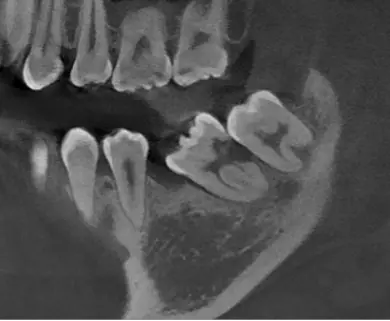

TOMOGRAFÍA DE DIENT​ES RETENIDO

Se da en casos de dientes que no completaron su proceso de erupció​n y su ubicación es compleja.